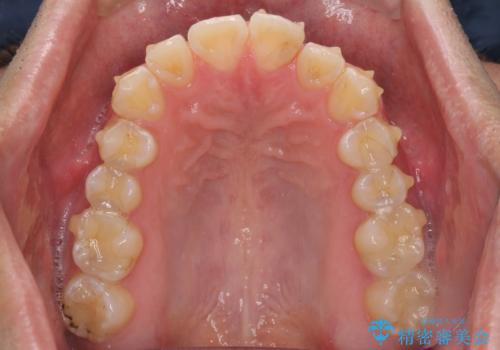

ディープバイトと叢生を解消 インビザライン矯正

- 前歯のデコボコを強い咬みしめを気にして来院された患者様です。

インビザラインを用いて、前歯の叢生を解消するとともに、ディープバイトを改善していくこととしました。

ディープバイトが改善されたことで、顎への負担が軽減され、更には上顎前歯の突出感も改善することができました。

矯正治療後には欠けてしまった修復物をセラミックインレーにて修復治療しました。